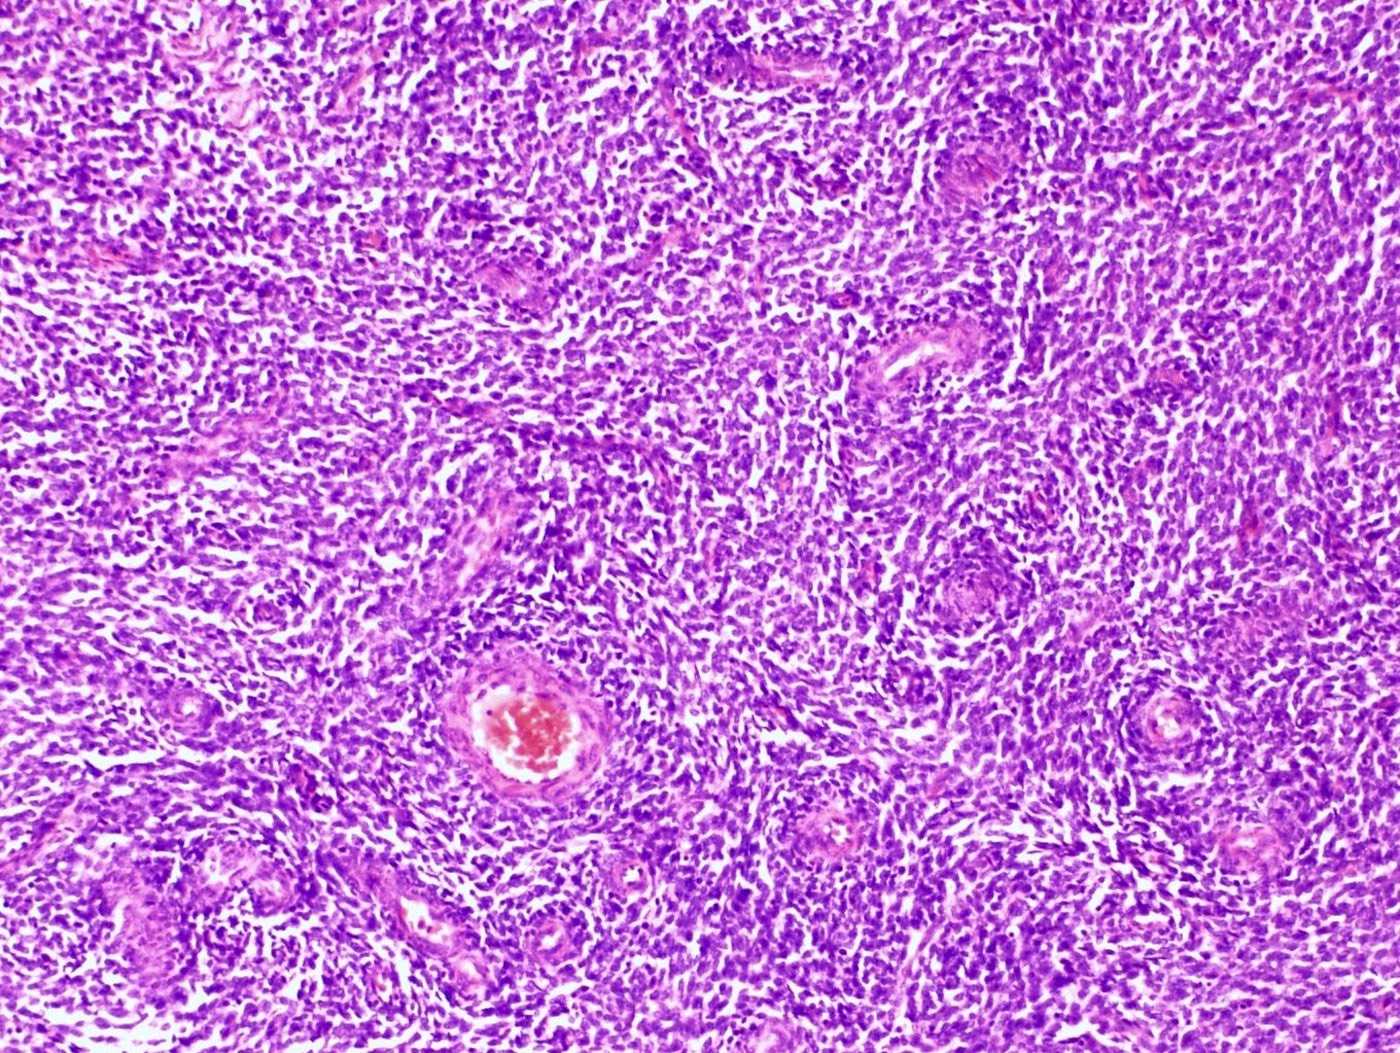

Microscopic (histologic) description

- Irregular cellular islands, forming permeative tongue-like pattern of myometrial invasion with frequent vascular invasion

- Monotonous oval to spindle cells with minimal cytologic atypia, vesicular chromatin and scant cytoplasm

- Mitotic count is usually low (< 5/10 high power fields), necrosis is usually absent

- Tumor cells may whorl around delicate arteriolar type vessels, reminiscent of proliferative phase endometrial stroma

- May have admixed collagen bands / plaques and foamy histiocytes

Microscopic (histologic) images

Contributed by Elizabeth Kertowidjojo, M.D., Ph.D., M.P.H. and Ayse Ayhan, M.D., Ph.D.